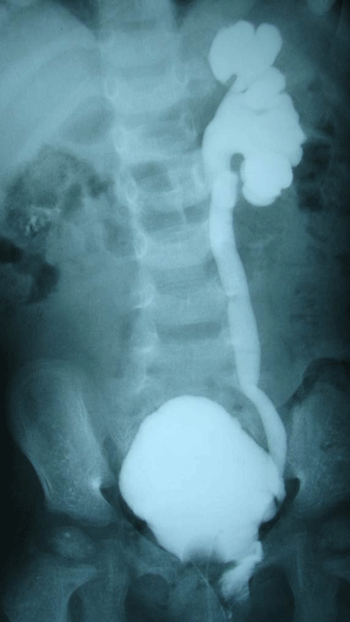

There were no deaths. Early postoperative complications included minor wound infection (n=1) and major wound infection with ventriculitis (n=1). Neurogenic bladder was seen in 1 patient who required vesicostomy 1 month after excision of SCT. She underwent vesicostomy closure at the age of 3 years and parents were advised clean intermittent catheterization (CIC). However, there was poor compliance to the suggested management and she developed recurrent urinary tract infections (UTI). At 6 years follow-up, her micturating cystourethrogram (MCUG) (Fig. 3) and radionucleiotide renal scan (DMSA) showed major vesicoureteric reflux (VUR) on left side and multiple scars in the left kidney. Increased frequency of stools was seen in 2 patients during the first few months after surgery.

Figure 3: MCUG showing VUR.